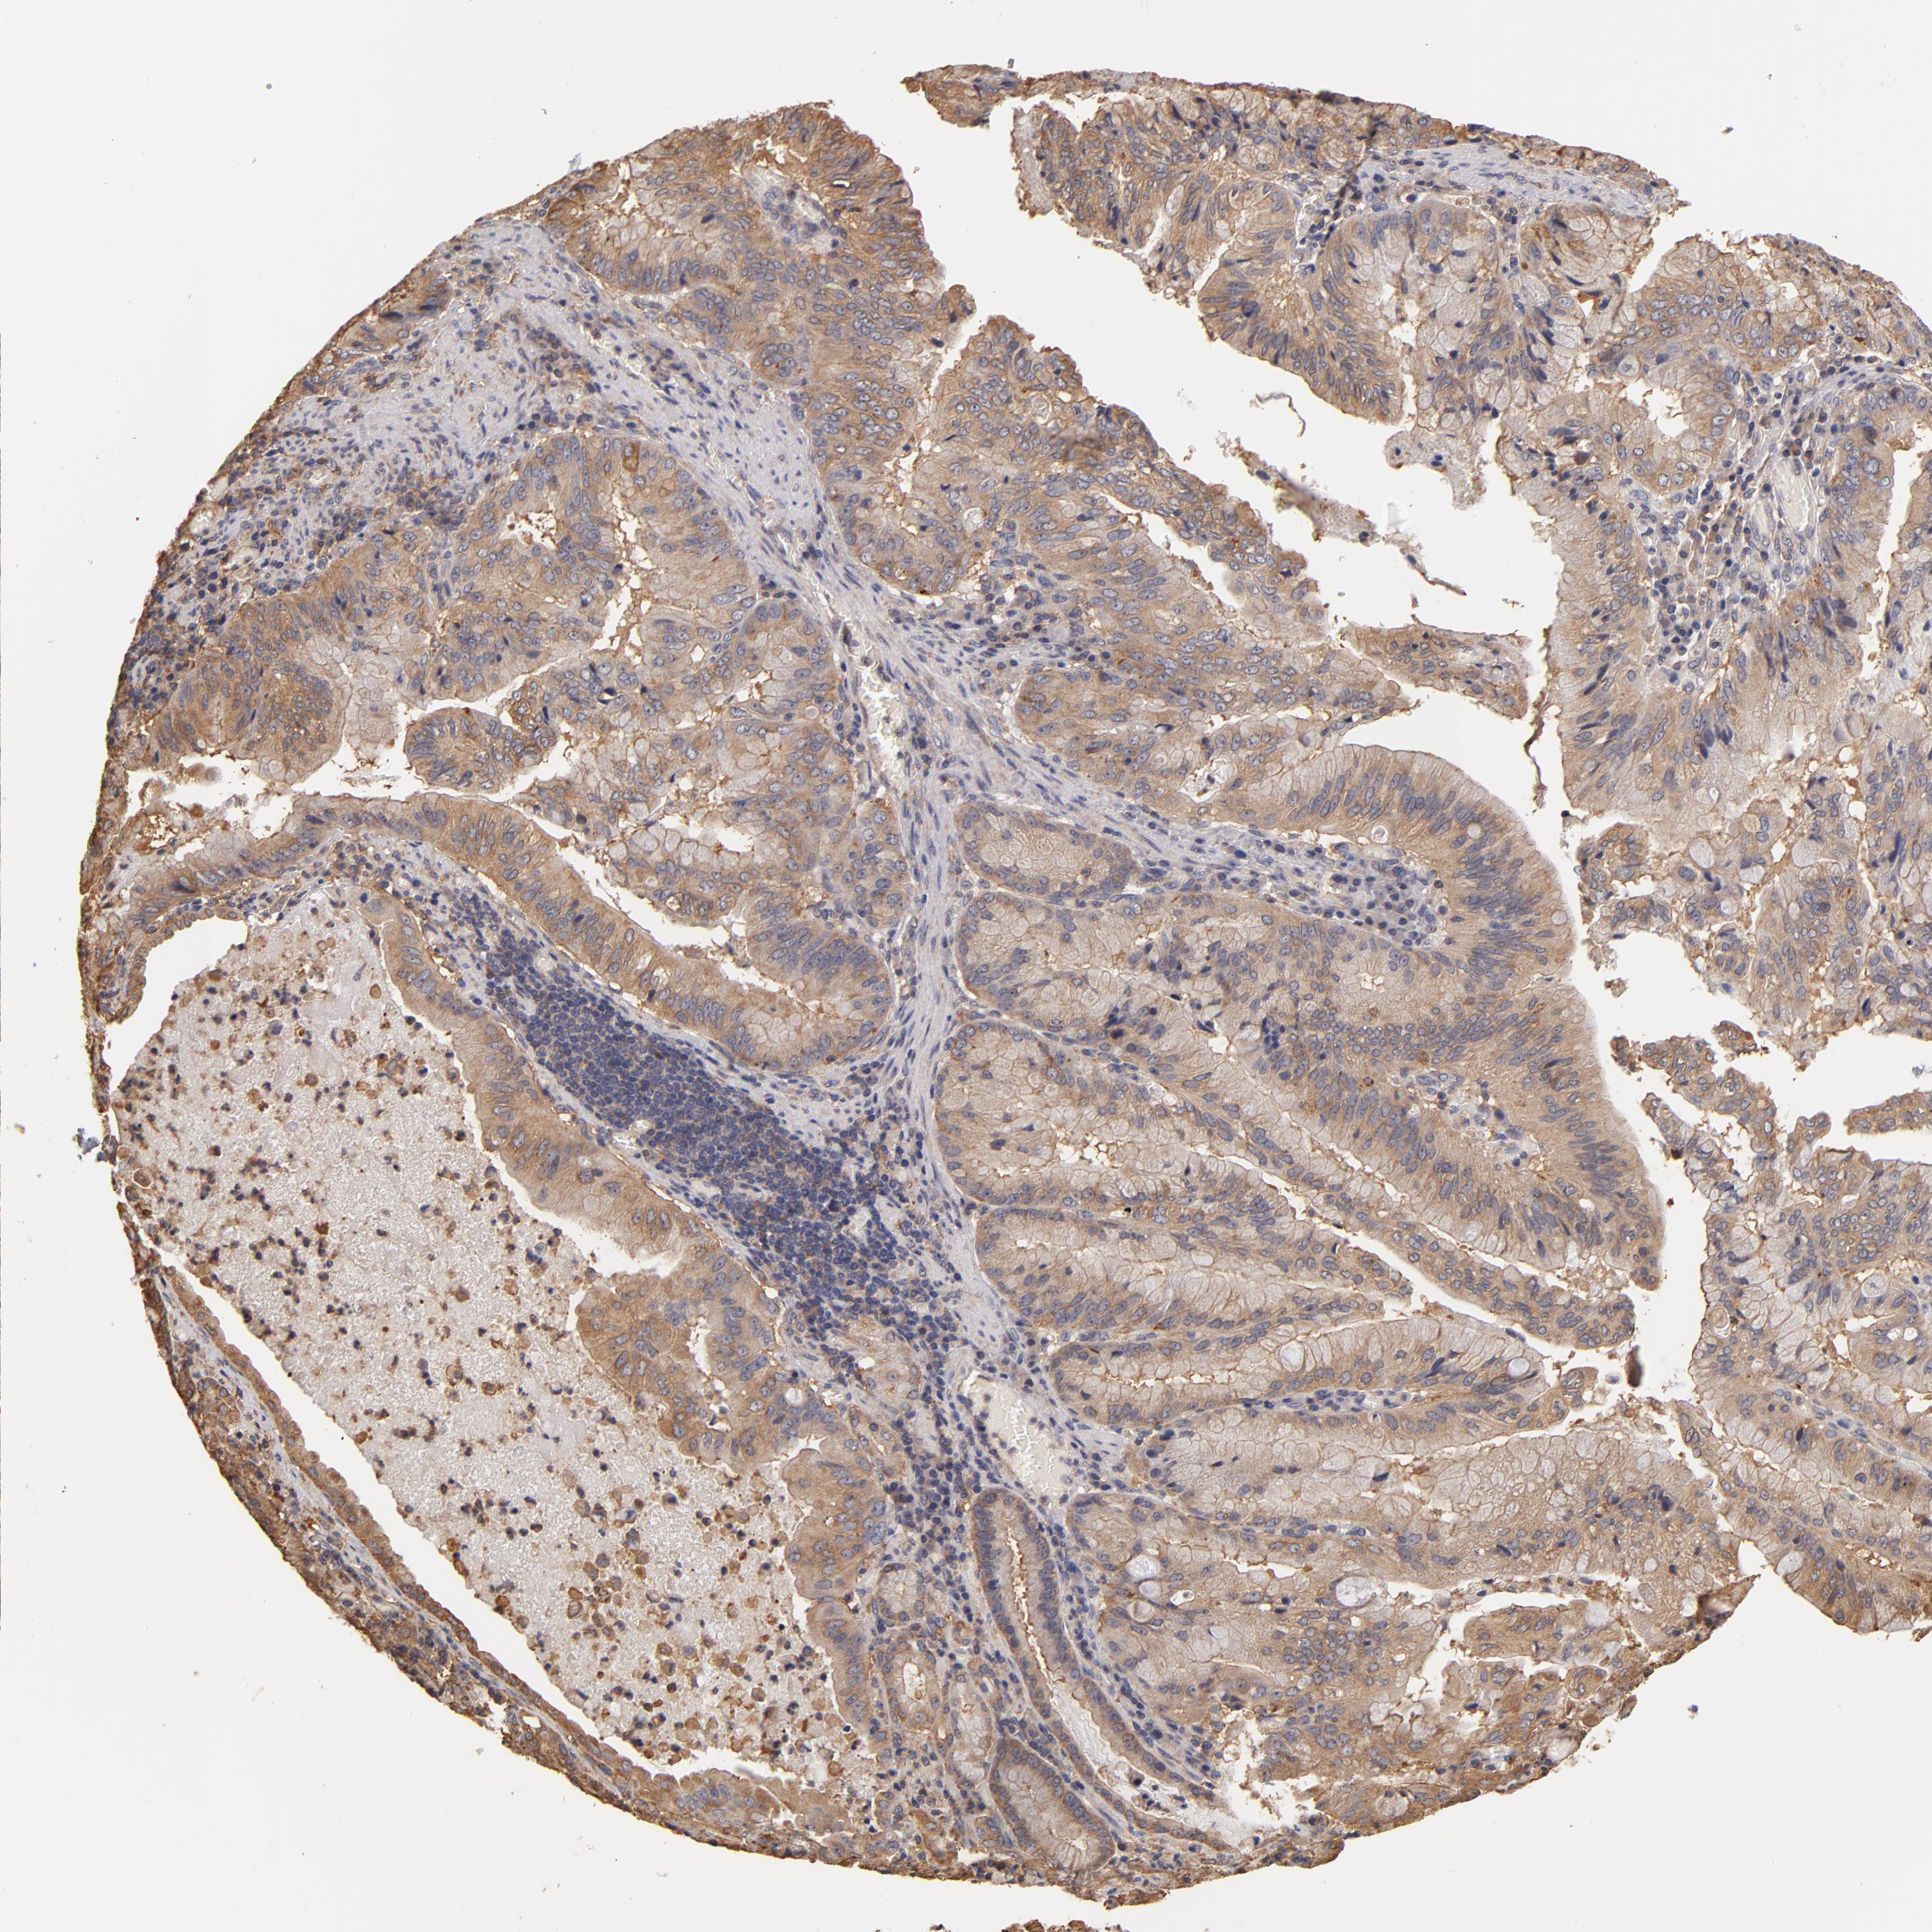

STOMACH CANCER - Protein expressioni

A mouse-over function shows sample information and annotation data. Click on an image to view it in a full screen mode. Samples can be filtered based on level of antibody staining by selecting one or several of the following categories: high, medium, low and not detected. The assay and annotation is described here.

Note that samples used for immunohistochemistry by the Human Protein Atlas do not correspond to samples in the TCGA dataset.

Antibody stainingi

Antibody staining in the annotated cell types in the current human tissue is reported as not detected, low, medium, or high, based on conventional immunohistochemistry profiling in selected tissues. This score is based on the combination of the staining intensity and fraction of stained cells.

Each image is clickable and will lead to virtual microscopy that enables deeper exploration of all samples and also displays staining intensity scores, fraction scores and subcellular localization as well as patient and tissue information for each sample.

Antibody HPA003910

Staining

High

Medium

Low

Not detected

Intensity

Strong

Moderate

Weak

Negative

Quantity

>75%

75%-25%

<25%

None

Location

Nuclear

Cytoplasmic/membranous

Cytoplasmic/membranous,nuclear

Adenocarcinoma, NOS